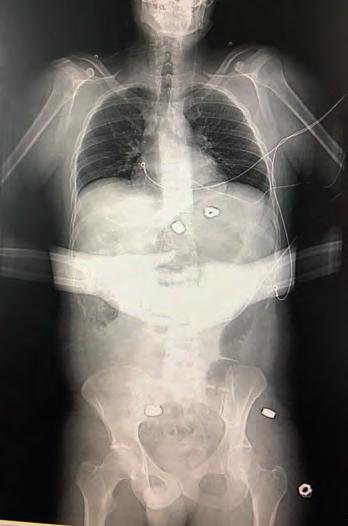

Martin with his wife, Gabby Martin’s x-ray after the bombing